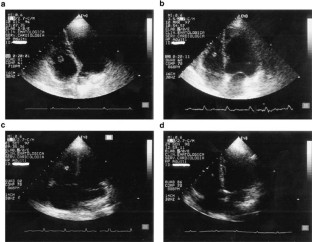

Torromeo, C., Latagliata, R., Avvisati, G. et al. Intraventricular thrombosis during all-trans retinoic acid treatment in acute promyelocytic leukemia. Leukemia 15, 1311–1313 (2001). https://doi.org/10.1038/sj.leu.2402156